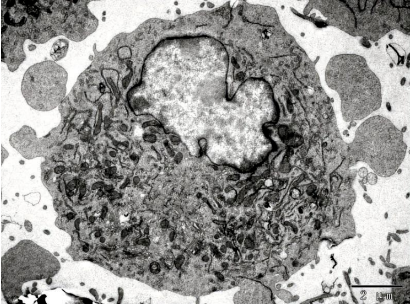

圖片來源:《腦腫瘤與神經組織電鏡圖譜》編著 孫異臨 人民衛(wèi)生出版社